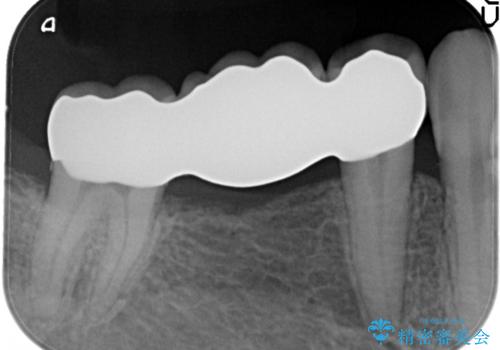

遠心根に歯根破折を認め、保存不可と判断しブリッジにて欠損補綴を行なっております。

今回は抜歯後、オールセラミックにて修復を行うことで審美性の高い治療を行うことができました。